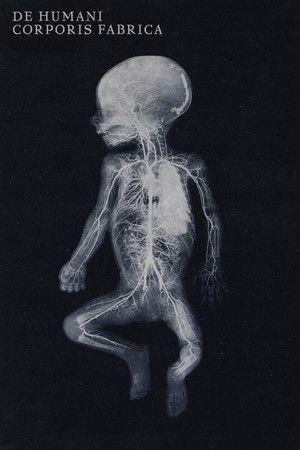

De humani corporis fabrica

(2023)Overview

An extraordinary adventure through the interior of the human body; or the discovery of an alien landscape of unprecedented beauty.

Original TitleDe humani corporis fabrica